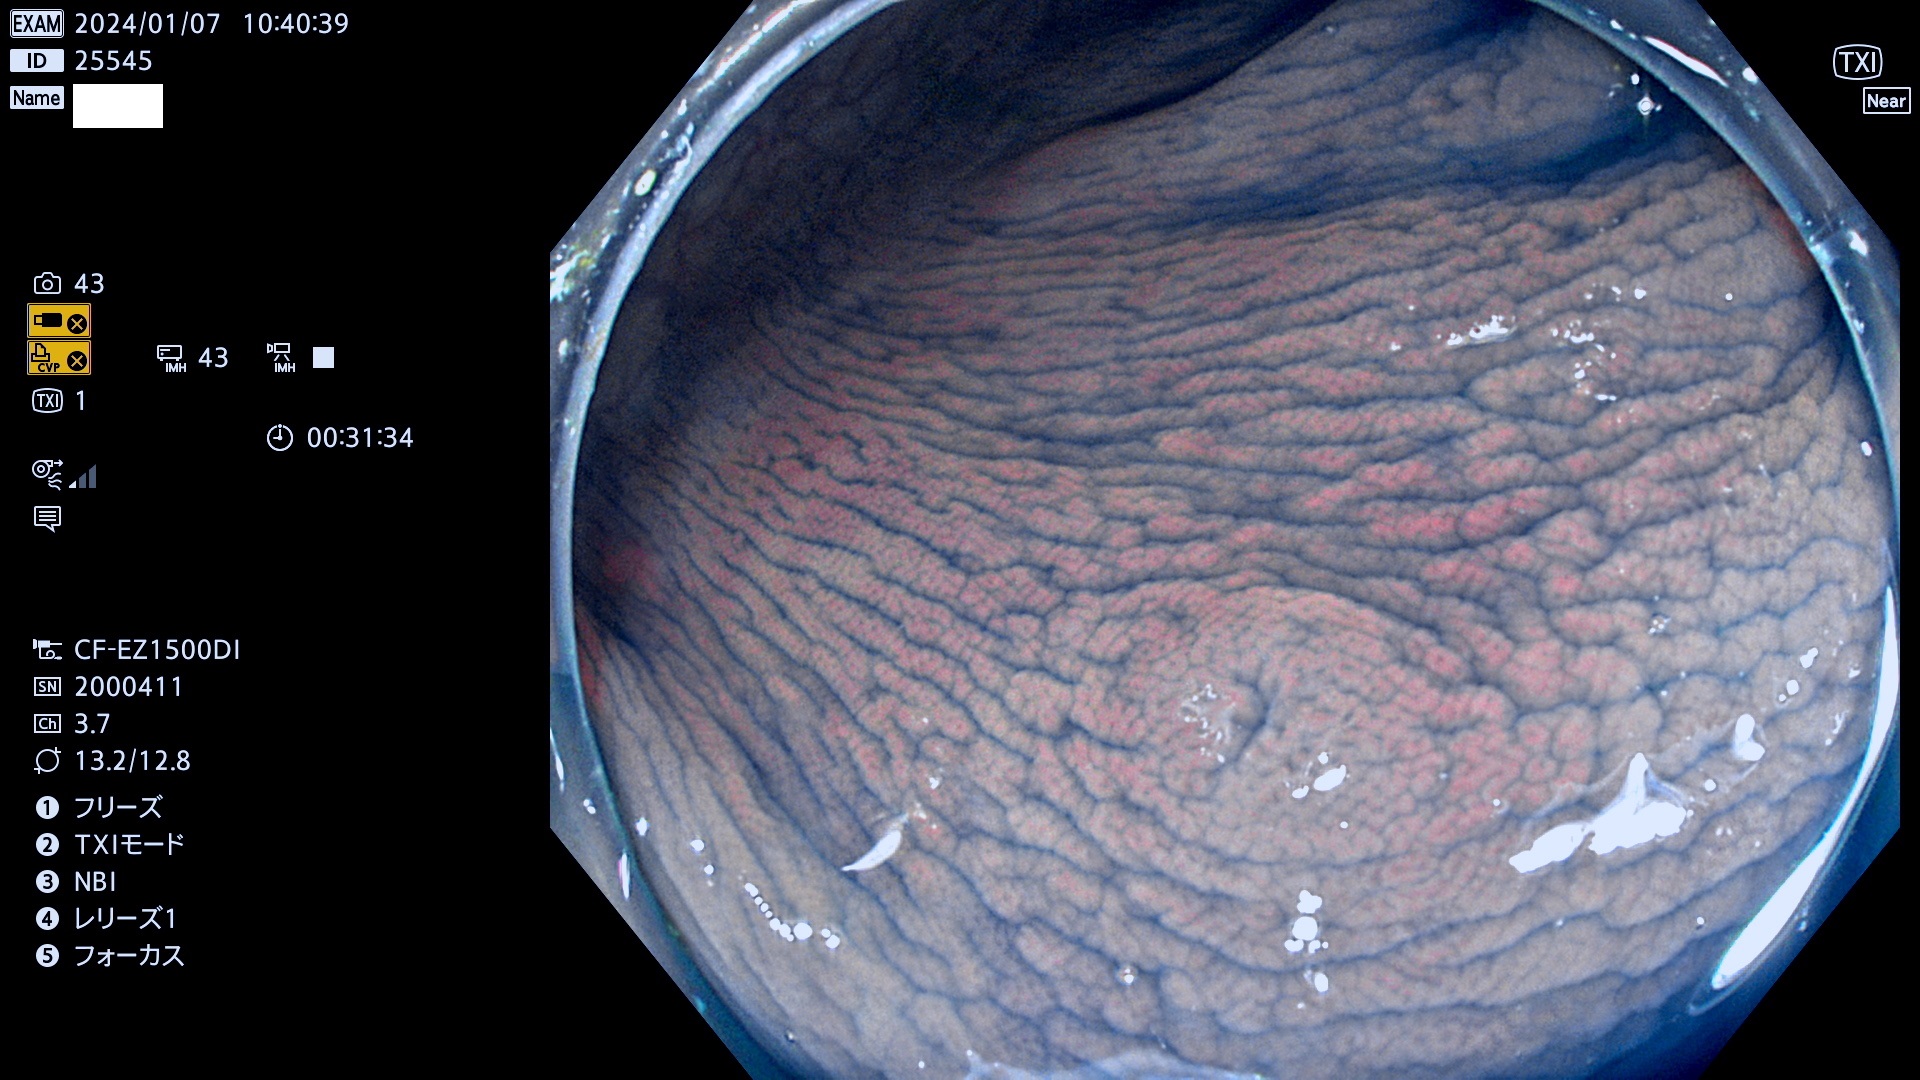

表面型腺腫(Flat Adenoma)の中で、完全に平坦な物をUb、陥凹している物をUcと呼びます。平坦隆起型(Ua)よりも、発見が難しく危険な病変です。

毎週の検査(木・金・土・日)に発見されたUb、Uc型・腺腫を、その週の日曜の夜にUPし1週間、提示します。

抽出の対象期間 2024年1月6日(土)〜1月8(月)の4日間(34件の検査)7件